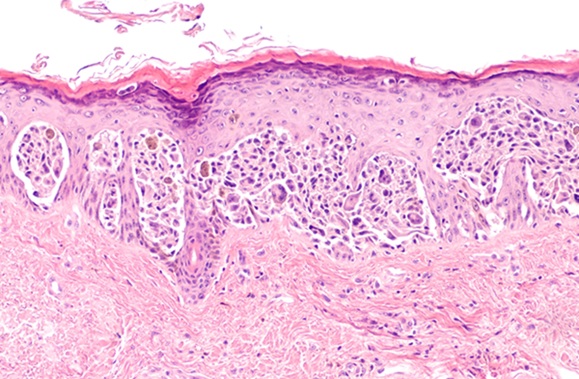

The current gold standard for diagnosis of renal involvement is a renal biopsy. While biopsies are highly informative, they cannot be serially repeated and come with attendant concerns, including the invasive nature of the procedure, and the possibility that the sample taken may not be representative of the entire kidney.